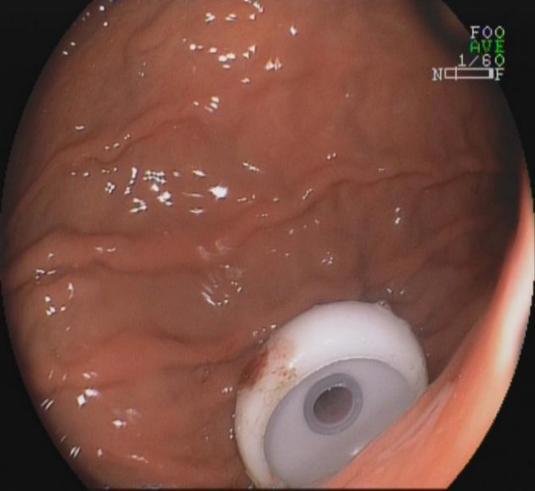

9.内镜下经皮胃造瘘术

我科是广西区内开展内镜下经皮胃造瘘最早的科室,在治疗上有十分丰富的经验。

内镜下经皮胃造瘘术是对于不能长期经口进食的患者和神经系统疾病的危重症患者,应用内镜下经皮胃造瘘术给予肠内营养具有独特的优势,可迅速恢复患者的胃肠功能,减少吸入性肺炎的发生,有效的延长生命。

胃造瘘胃体内一端